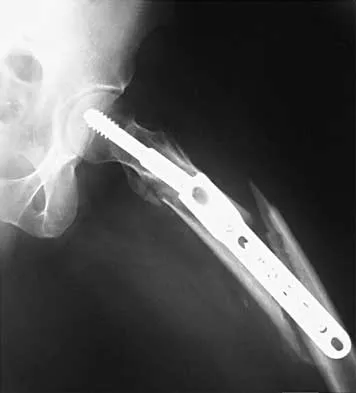

Figures 7a and 7b show the radiographs of a 51-year-old woman who injured her left leg after falling off a stepladder. Surgical reconstruction is performed with a compression screw and side plate; the postoperative radiograph is shown in Figure 7c. Following gradual progression of weight bearing, she reports that she slipped again and placed full weight on the extremity. She now notes a new onset of increased pain in her left thigh and hip region. Follow-up radiographs are shown in Figures 7d and 7e. Reconstruction should consist of

Explanation

The initial fracture was an unstable reverse oblique intertrochanteric fracture with subtrochanteric extension. Initial fixation with a high-angled screw and side plate construct may not provide stability as well as a 95 degree fixed-angle device or a intramedullary hip screw device. The follow-up radiographs show loss of fixation and further propagation of the fracture distally. Reconstruction would best be accomplished with hardware removal and conversion to a long intramedullary nail with femoral head fixation or a 95 degree angled plate and screw device. Conversion to a longer plate does not improve the biomechanical situation at the primary fracture site. In situ bone grafting would not provide any additional stability and would not correct the deformity. The proximal femoral fracture is not amenable to retrograde nailing. Cerclage wiring will not sufficiently enhance stability and is not indicated. Bridle SH, Patel AD, Bircher M, Calvert PT: Fixation of intertrochanteric fractures of the femur: A randomized prospective comparison of a gamma nail and dynamic hip screw. J Bone Joint Surg Br 1991;73:330-334. DeLee JC: Fractures and dislocations of the hip, in Rockwood CA Jr, Green DP, Bucholz RW, Heckman JD (eds): Rockwood and Green's Fractures in Adults, ed 4. Philadelphia, PA, Lippincott-Raven, 1996, pp 1659-1825. Haidukewych GJ, Israel TA, Berry DJ: Reverse obliquity fractures of the intertrochanteric region of the femur. J Bone Joint Surg Am 2001;83:643-650.